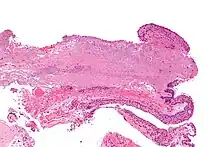

Pathology

Pterygium in the conjunctiva is characterized by elastotic degeneration of collagen (actinic elastosis[12]) and fibrovascular proliferation. It has an advancing portion called the head of the pterygium, which is connected to the main body of the pterygium by the neck. Sometimes a line of iron deposition can be seen adjacent to the head of the pterygium called Stocker's line. The location of the line can give an indication of the pattern of growth.

The pterygium is composed of several segments:

- Fuchs' Patches (minute gray blemishes that disperse near the pterygium head)

- Stocker's Line (a brownish line composed of iron deposits)

- Hood (fibrous nonvascular portion of the pterygium)

- Head (apex of the pterygium, typically raised and highly vascular)

- Body (fleshy elevated portion congested with tortuous vessels)

- Superior Edge (upper edge of the triangular or wing-shaped portion of the pterygium)

- Inferior Edge (lower edge of the triangular or wing-shaped portion of the pterygium).